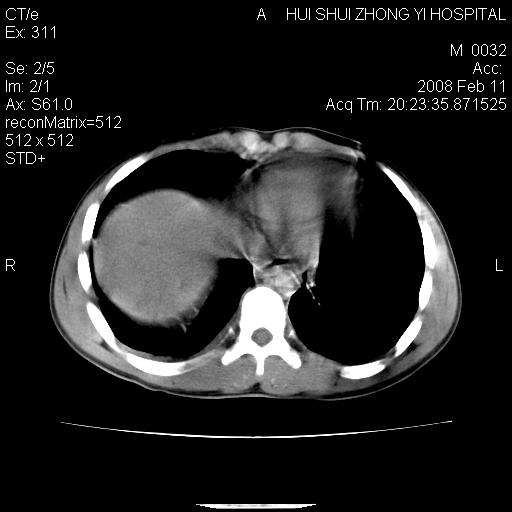

8年前曾在贵洲省人民医院b超诊断为肝内胆管结石。现腹痛剧烈,现发烧、头痛、恶心呕吐县医院b超示胆囊肿大大小159*46mm,囊内见6*5mm强回声光团,胆各总管内径56mm。提示:胆囊结石、急性胆囊炎、胆总管重度扩张。

胆囊结石.急性胆囊炎.重度胆管扩张.右侧胸腔少量积液,建议ct增强

考虑先天性胆管囊肿;胆囊增大并结石。右侧胸腔少量积液,建议ct增强。

先天性胆管囊肿,胆囊结石、胆囊增大,右侧少量胸腔积液。